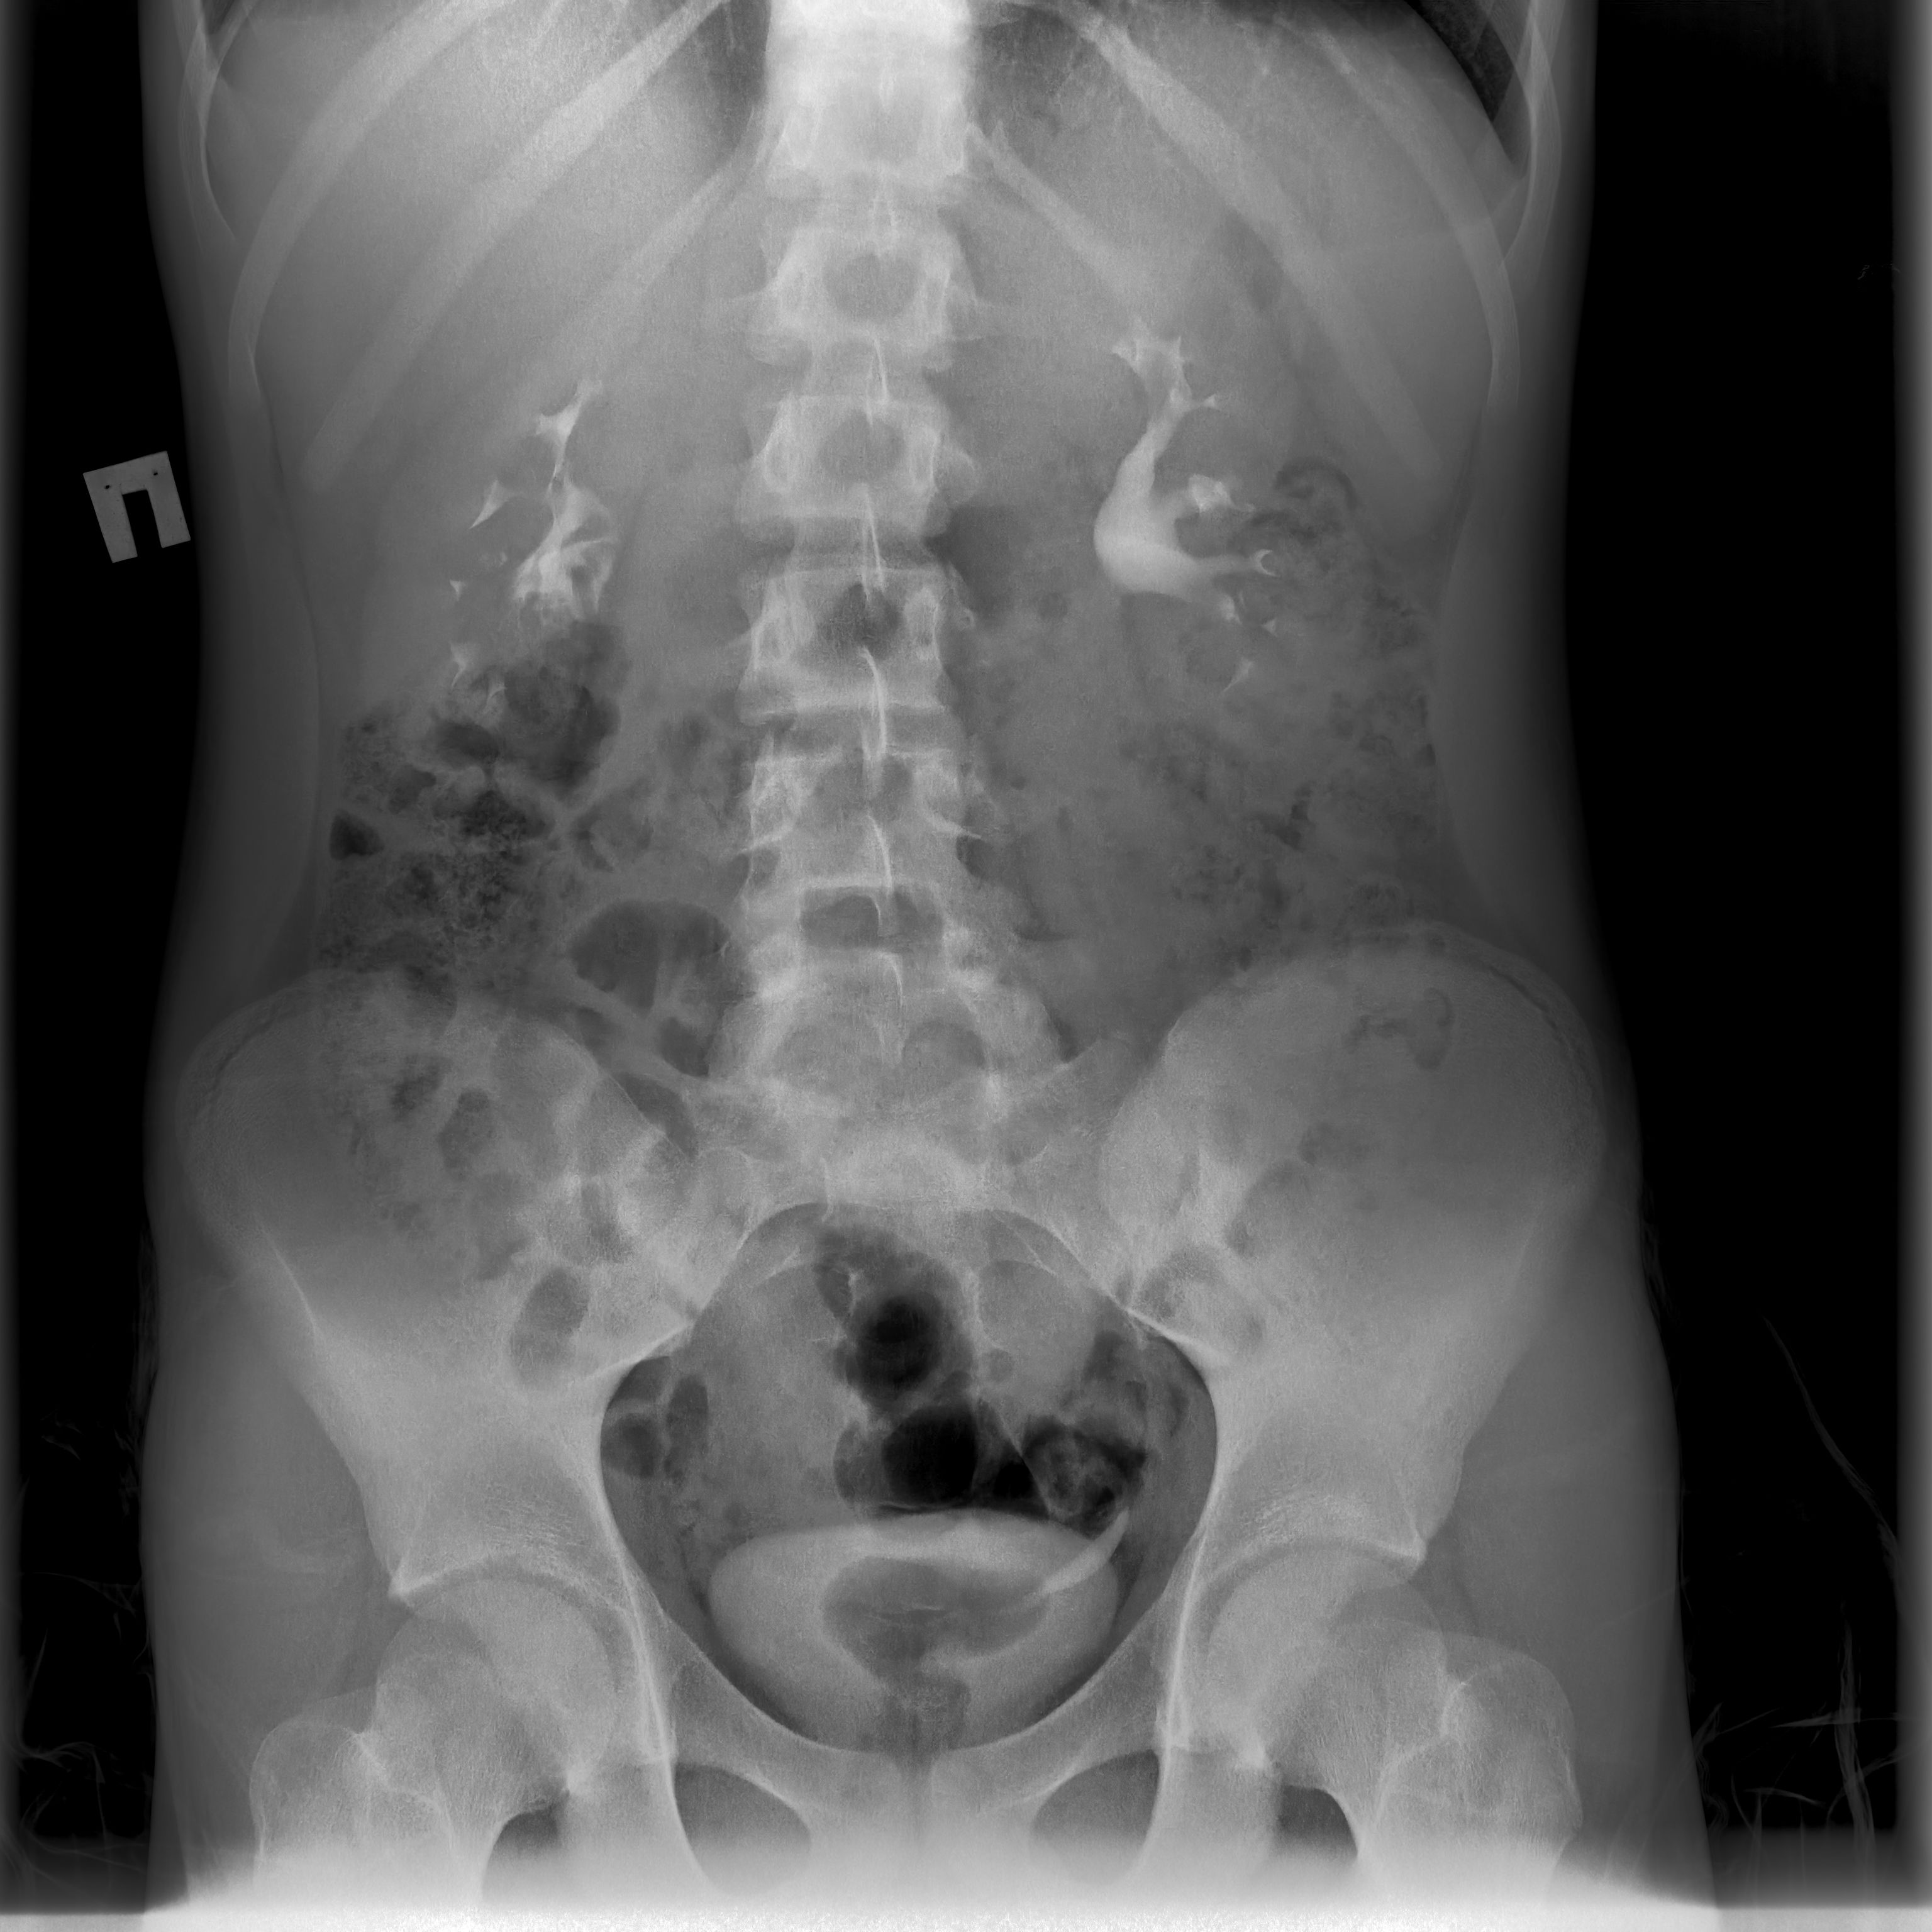

В урологическое отделение экстренно госпитализирован подросток с жалобами на острую боль в животе. В ходе обследования врачи детской окружной больницы Нижневартовска выявили у подростка нефроптоз высокой степени, осложненный гидронефрозом – почка из своего физиологического местоположения опускалась в малый таз, вызывая выраженный болевой синдром и ухудшая отток мочи. «Нефроптоз у подростков – частое явление. Низкие степени, как правило, лечатся путем назначения общих рекомендаций, направленных на укрепление передней брюшной стенки: плавание, укрепление пресса, корректировка питания с целью увеличения подкожно жировой клетчатки, чтобы жировая капсула фиксировала почку. Так как у нашего пациента из-за заболевания началось осложнение – гидронефроз, мы выбрали более активную тактику – хирургическое лечение, направленное на фиксацию почки в необходимом положении», - рассказал Николай Обухов, заведующий детским уроандрологическим отделением Нижневартовской окружной клинической детской больницы.

Заведующий уроандрологическим отделением Николай Обухов и врач-уролог Руслан Муллагалиев установили сетчатый имплант, в который поместили почку, и зафиксировали его к поясничной мышце. Пациент провел несколько дней в отделении и был выписан на амбулаторное наблюдение с положительной динамикой – отсутствием болевого синдрома и расстройством мочеиспускания. «Операция прошла без осложнений, длилась не больше часа. Ребенок, миновав реанимацию, находился под наблюдением урологов. Спустя два месяца после проведения операции ребенок был госпитализирован к нам в отделение для проведения контрольного обследования. У нашего пациента нефроптоз не выявлен», - рассказал Николай Обухов.